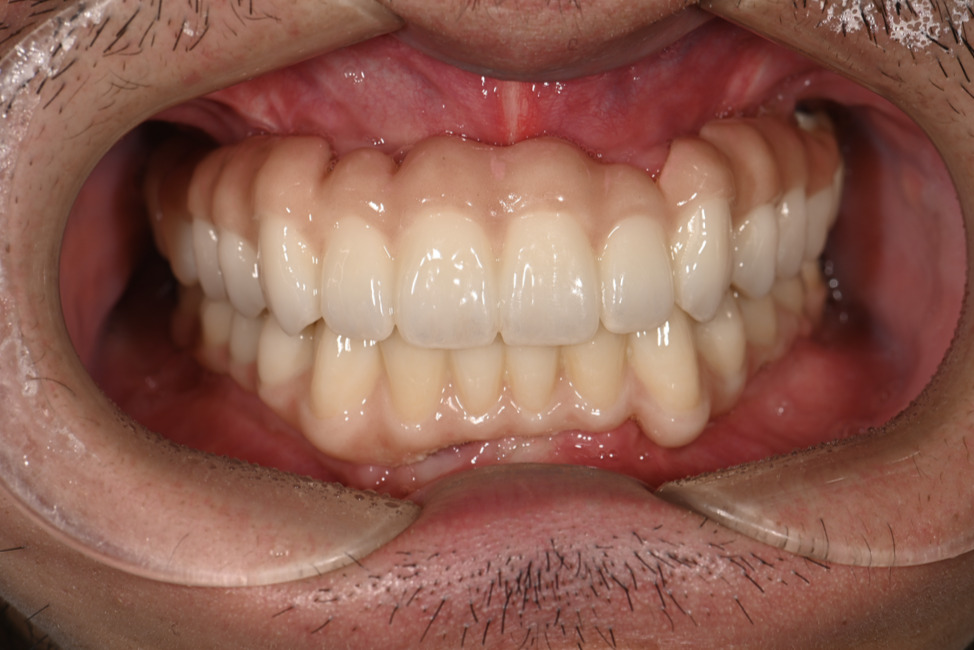

| 主訴 | 全体的にきれいにしたい |

|---|---|

| 治療内容 | 午前中に上下顎共に重度の歯周病、虫歯のため全ての歯を抜歯させていただき下顎はインプラントの土台を3本埋入し歯型を取り午後に上部構造(下顎全ての歯)を装着、上顎は一度総入れ歯を装着させていただきました。 治療が1日で完了しその日のうちに噛めるようになります。 |

| 治療期間 | 2回(1回目に資料取りをさせていただき2回目に下記の全ての治療をさせていただきました。) |

| 治療費 | 250万円 |

| 治療 リスク | 抜歯した部位などに関しては当日痛みが出ますので痛み止めなどを処方させていただきます |